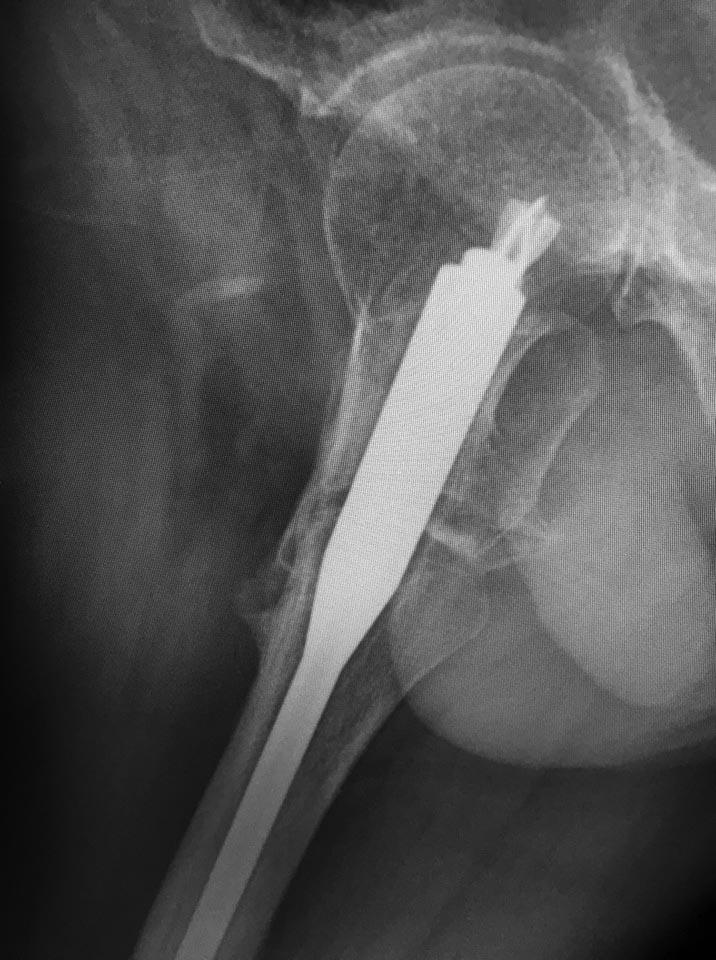

Несращение межвертельного перелома

доброго времени суток! как бы вы поступили в данном случае? Пациент 52 года, синтез 7 мес назад, ходьба с костылями.

Боль при ходьбе. Два дистальных блокируемых винта в статике ( срезалось на фото)

Уважаемый коллега, я бы попробовал реостеосинтез. Взял бы стержень интертан smith nephew, дал компрессию между отломками. В головке достаточно места, лезвие изначально установлено короткое.

Надо сделать notching. То есть вырубить ниже шеечного винта паз в латеральной стенке.

Надо сделать дефект латерального кортекса высотой мм 10-15 шириной в этот винт прямо дистальнее винта, чтобы под ним была не стенка, а дырка. Удалить дистальные винты. И сколотить на столе. И либо оставить без винтов, либо динамический ввести, если есть сильные ожидания ротационной подвижности. Скорее всего, и он не нужен.

Или еще один вариант - заменить клинок на более короткий, и ввести его так, чтобы он латеральнее гвоздя не выстоял. И даже этот, наверно, можно просто поглубже пробить - места в головке хватает.